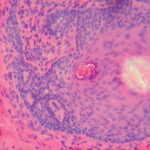

BCC with squamous differentiation =الورم القاعدي الخلايا مع تمايز شائك